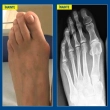

Cum poate fi evitată recidiva monturilor piciorului după intervenția chirurgicală?11-11-20201.103Sănătate